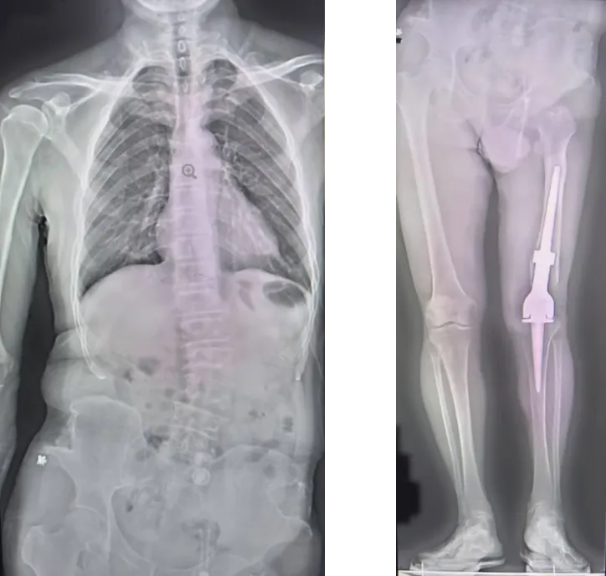

X光对比图清晰显示:李先生左股骨解剖轴仅38.8cm(右侧46.7cm),左下肢机械轴较右侧短缩达10.4cm。这意味着——

原本改善生活质量的手术,因假体松动等问题,反而造成了左下肢屈曲挛缩畸形。长期代偿性弯腰让他的脊柱弯成"C"型,关节僵硬和持续疼痛更是彻夜难眠。

术后复查显示,患者的膝关节假体位置良好,符合生物力学要求,患者的下肢长度差异也得到了明显的改善。

术后对比X光显示,假体的位置恰到好处,患者的下肢机械轴已达预期重建目标。